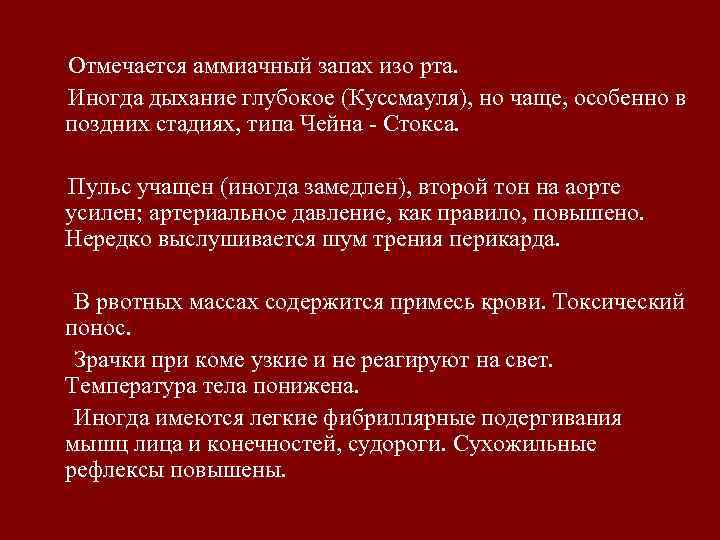

Отмечается аммиачный запах изо рта. Иногда дыхание глубокое (Куссмауля), но чаще, особенно в поздних стадиях, типа Чейна - Стокса. Пульс учащен (иногда замедлен), второй тон на аорте усилен; артериальное давление, как правило, повышено. Нередко выслушивается шум трения перикарда. В рвотных массах содержится примесь крови. Токсический понос. Зрачки при коме узкие и не реагируют на свет. Температура тела понижена. Иногда имеются легкие фибриллярные подергивания мышц лица и конечностей, судороги. Сухожильные рефлексы повышены.

Отмечается аммиачный запах изо рта. Иногда дыхание глубокое (Куссмауля), но чаще, особенно в поздних стадиях, типа Чейна - Стокса. Пульс учащен (иногда замедлен), второй тон на аорте усилен; артериальное давление, как правило, повышено. Нередко выслушивается шум трения перикарда. В рвотных массах содержится примесь крови. Токсический понос. Зрачки при коме узкие и не реагируют на свет. Температура тела понижена. Иногда имеются легкие фибриллярные подергивания мышц лица и конечностей, судороги. Сухожильные рефлексы повышены.